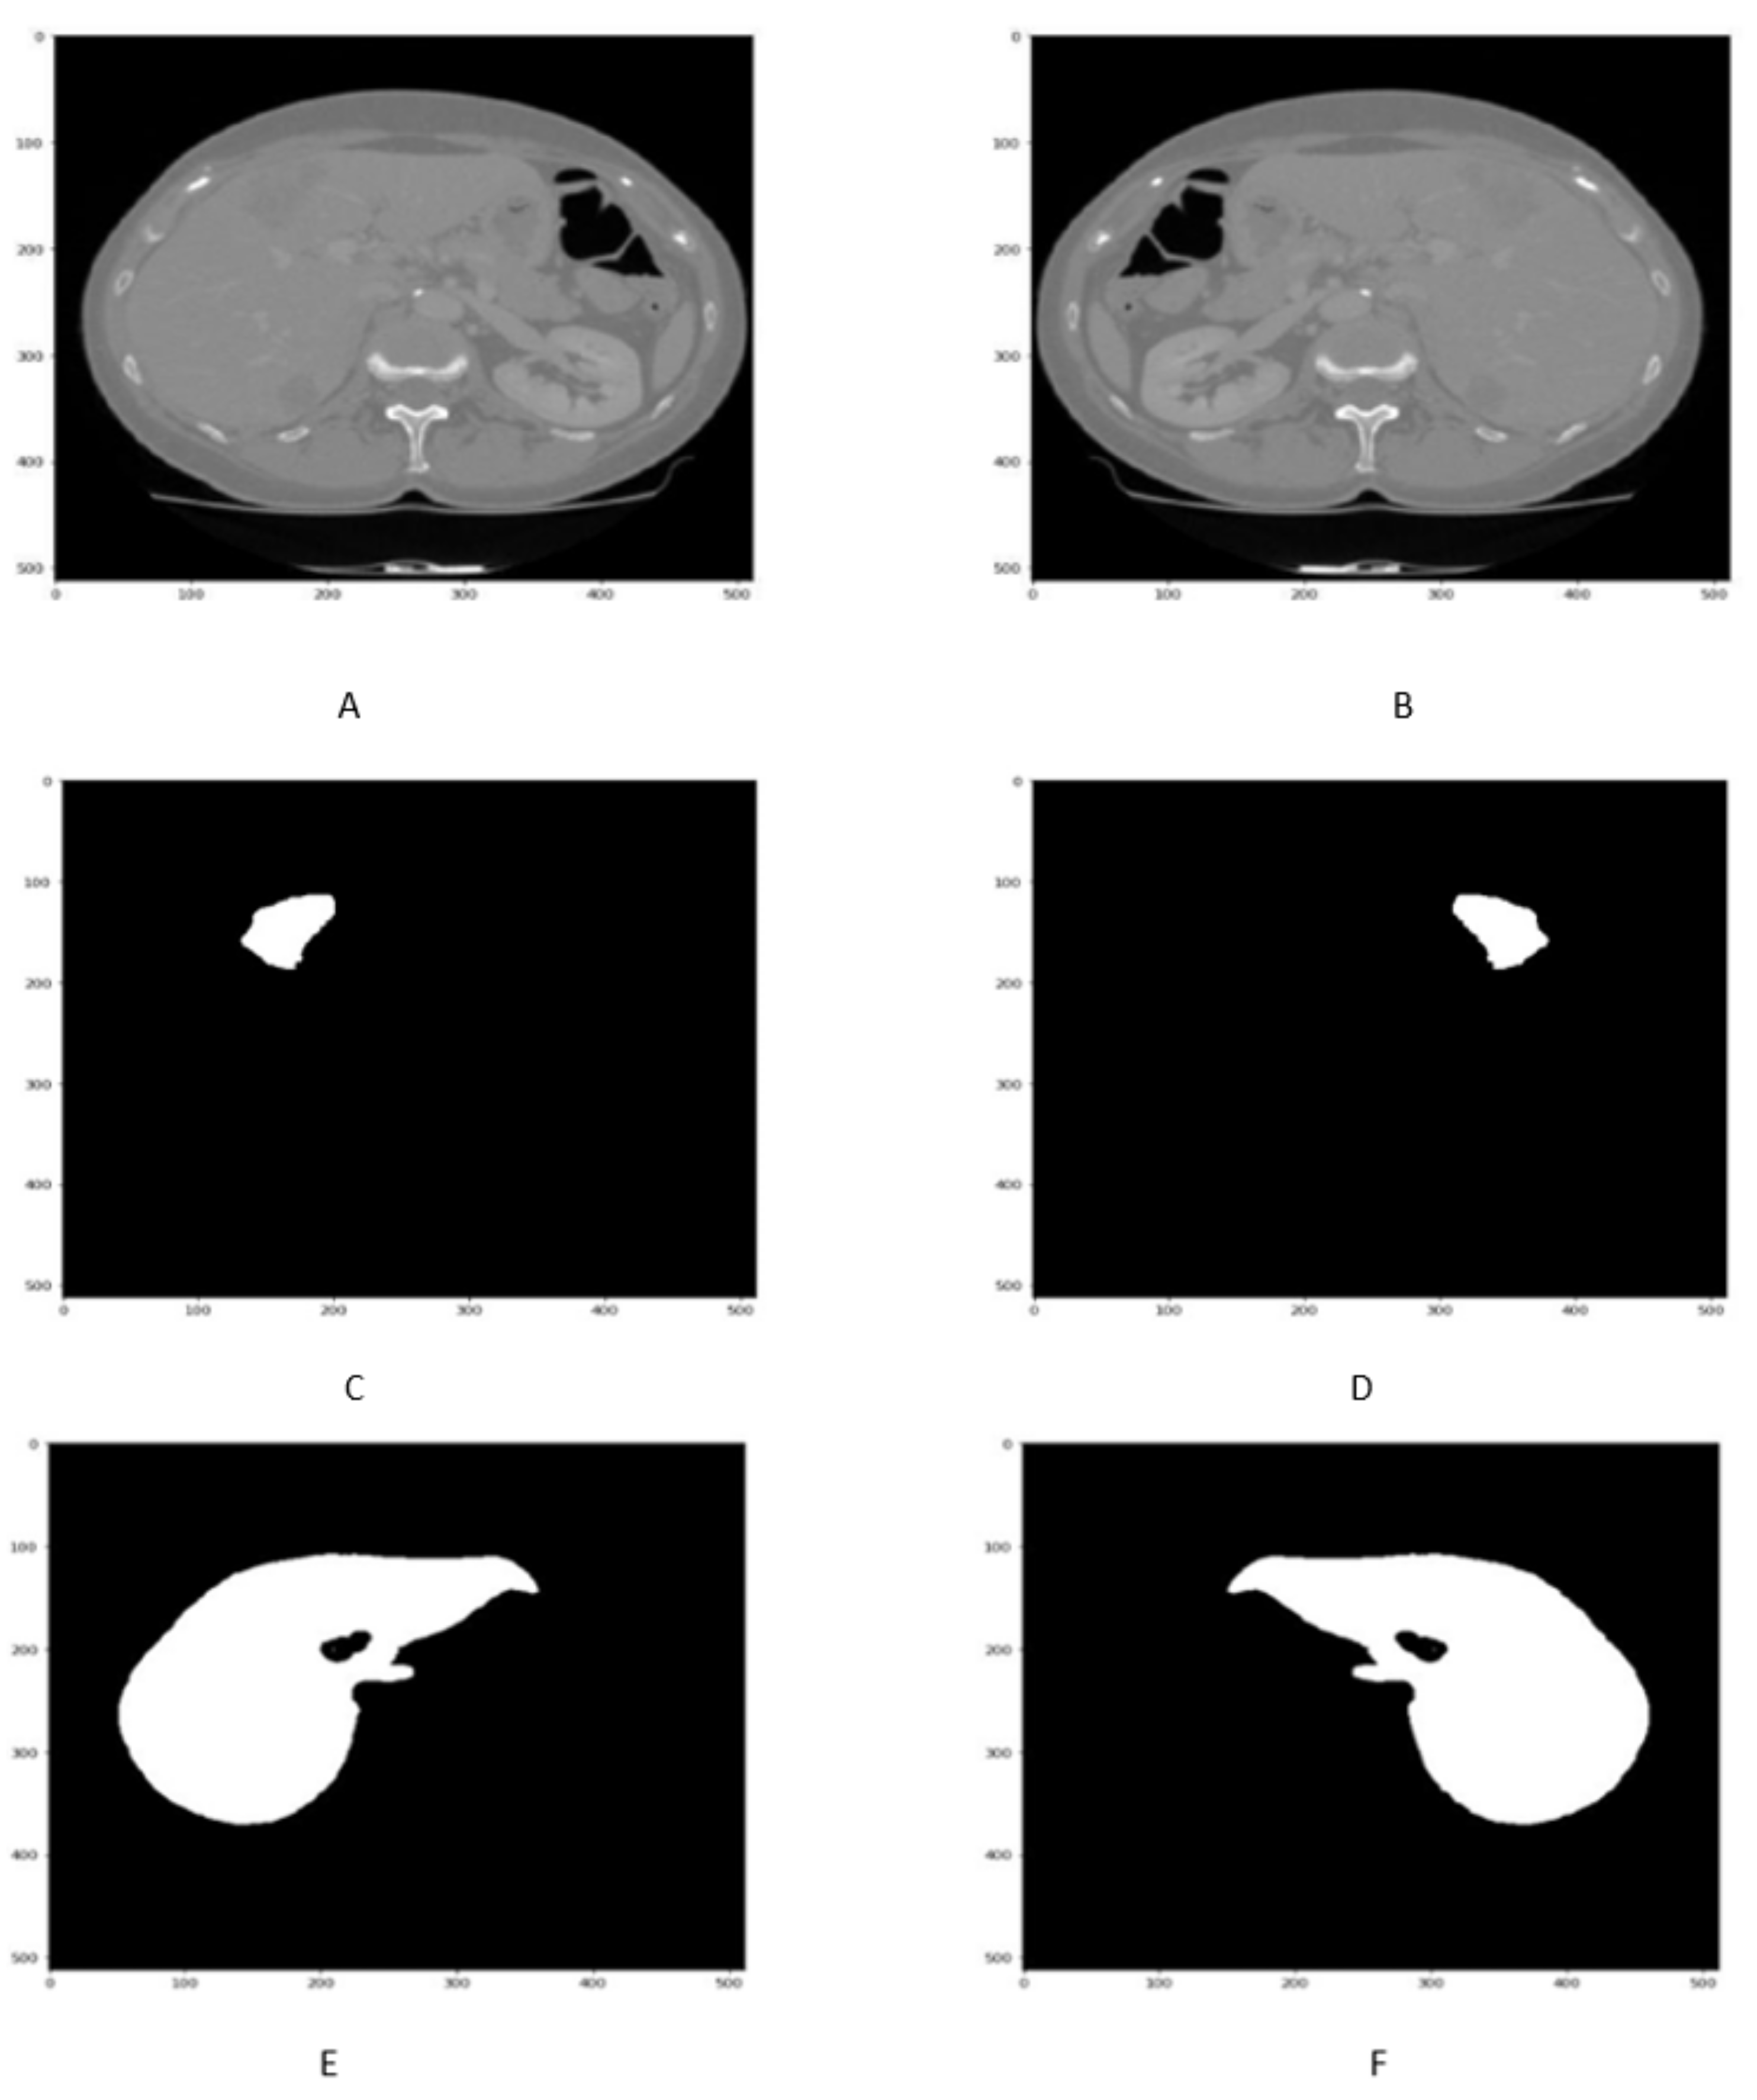

Reflection is a data augmentation technique in which the image can be flipped across the x or y-axis to generate more samples for network training. In order to avoid the computational expense, the liver images along with its tumor masks are reflected as shown in Figure 4A–F.

Figure 4.

Figure shows that the Liver scan tumor mask before 90 in (A,C,E) While liver scan and tumor mask in (B,D,F) after reflection.

The rotation method of data augmentation involves rotating the image to a certain degree that can be considered a new image.Here, a 90 rotation of liver images along with its masks are performed as shown in Figure 5A–F.

Figure 5.

Figure shows that the liver slice and its masks before 90 in (A,C,E) rotation, While liver scan and its masks mask in (B,D,F) after rotation.